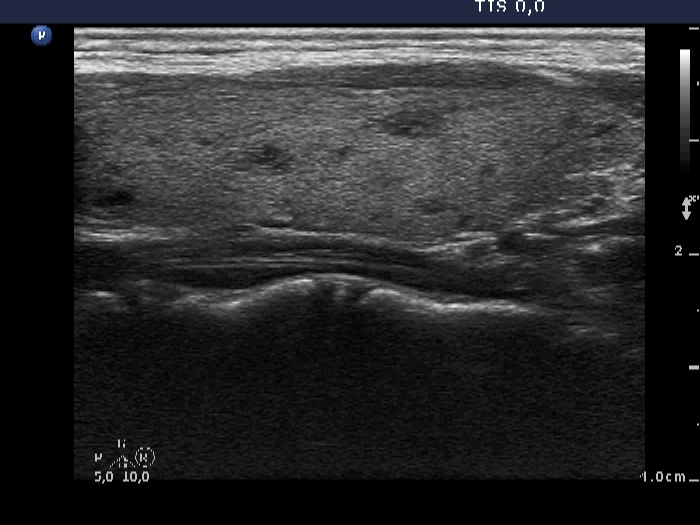

Right lobe, longitudinal scan

Left lobe, longitudinal view. The echogenicity index is around 10%.